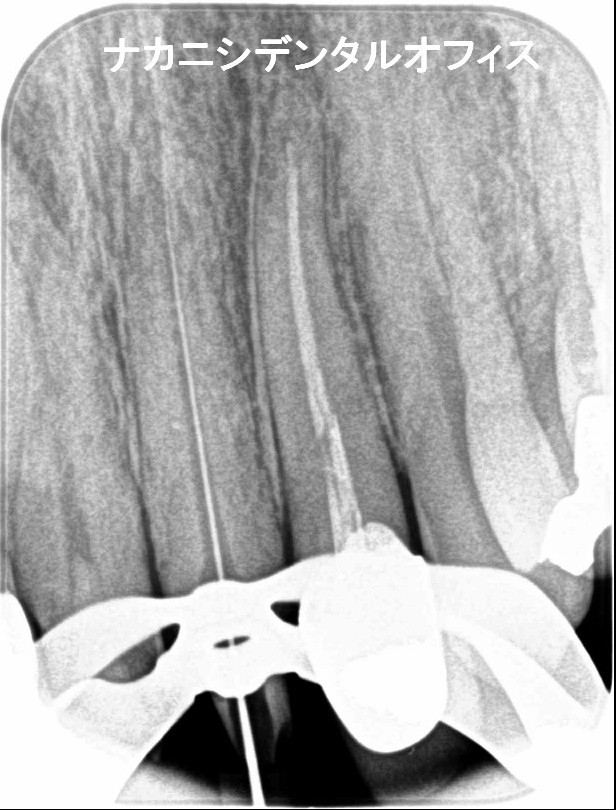

当院では、マイクロスコープを使用した、精度の高い治療を受けていただけます。また歯内療法専門医が月3~4回ほど来られ院内でラバーダムを必須として治療をおこなっております。

マイクロスコープとは、手術用の顕微鏡のこと。肉眼の20倍以上に拡大して患部を診ることが可能です。

当院ではこのマイクロスコープを使い、虫歯になっている箇所にピンポイントでアプローチ。虫歯を取り残すことなく、きれいに除去します。

精密な治療で、虫歯になっている最小限の箇所のみ削り、 患者さまの歯や神経を守りながら治療をしています。

マイクロスコープを使用することによって、肉眼では見えない歯の根の中や歯質と人工の歯の境目を高倍率で確認することができます。

それによって、不要に削り過ぎたり、逆に細菌に感染した組織を除去しきれなかったりすることが少なくなり、最小限の侵襲(Minimum Intervention)による治療を行うことができます。

また、肉眼では確認しにくい歯のひびや歯質と人工歯の境目の適合度合いを確認するのにも非常に有効な医療機器です。